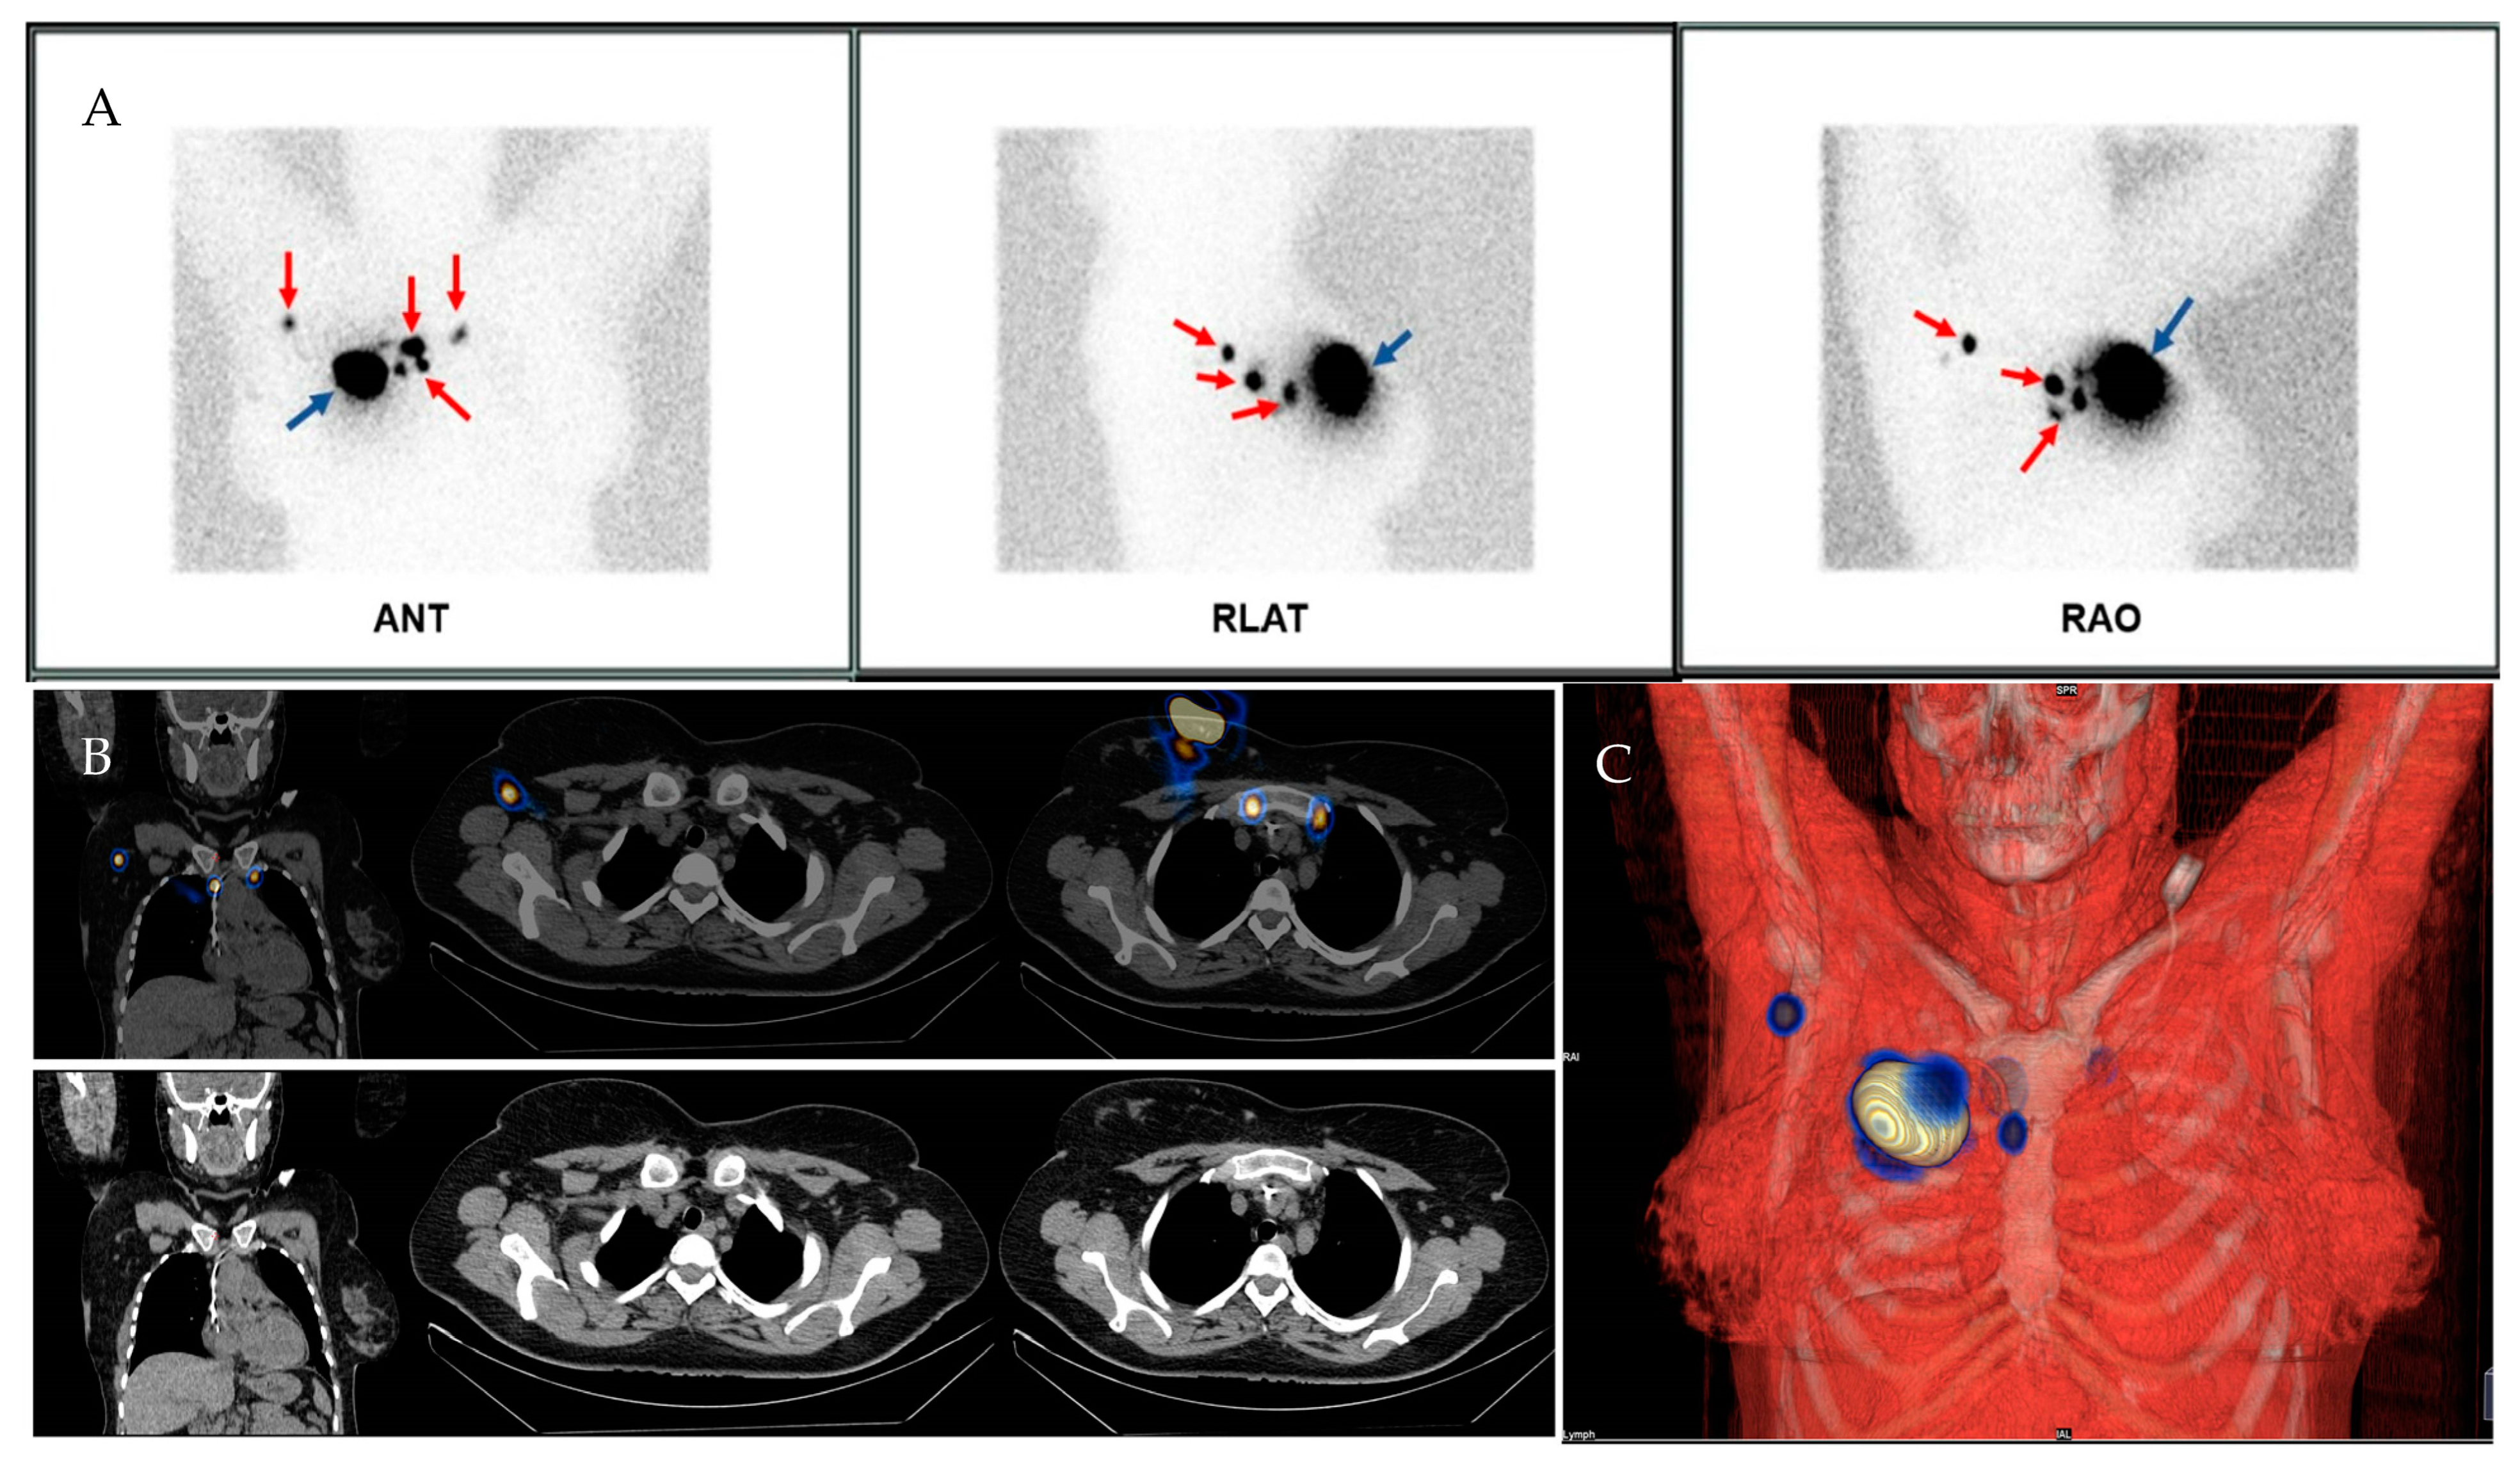

2.1.3. Imaging Acquisition Technique

2.1.4. Intraoperative SLN Identification